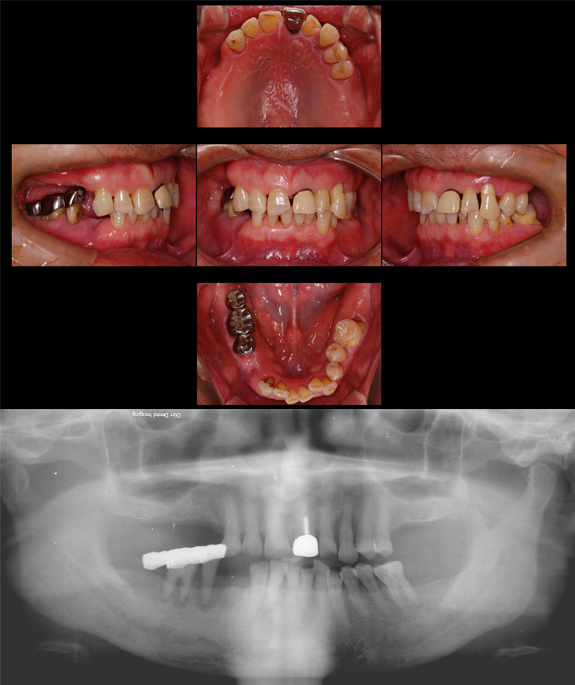

症例4

術前

準備中

術後